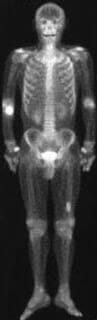

It went well. The doc says they didn’t need to take any cells from his pelvis. They got some from the other bone in his forearm (ulna). The damged bone (radius) is wired together again now, and will start on the the Pamindronate therapy in a couple of weeks.